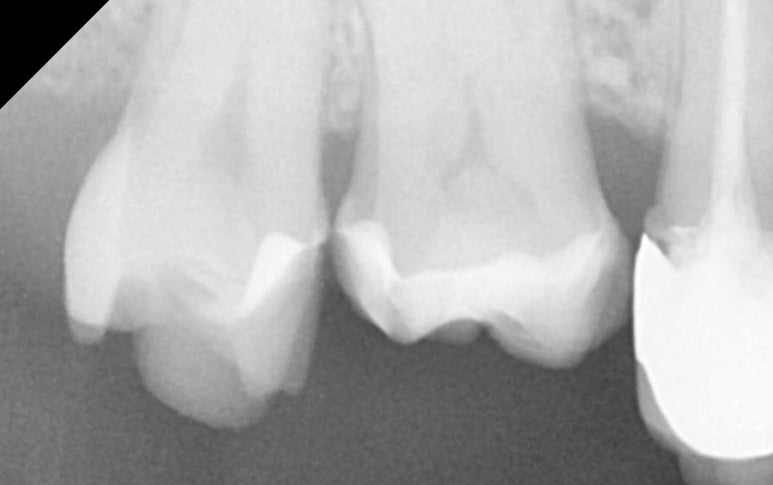

25.11.19 접착 후 엑스레이